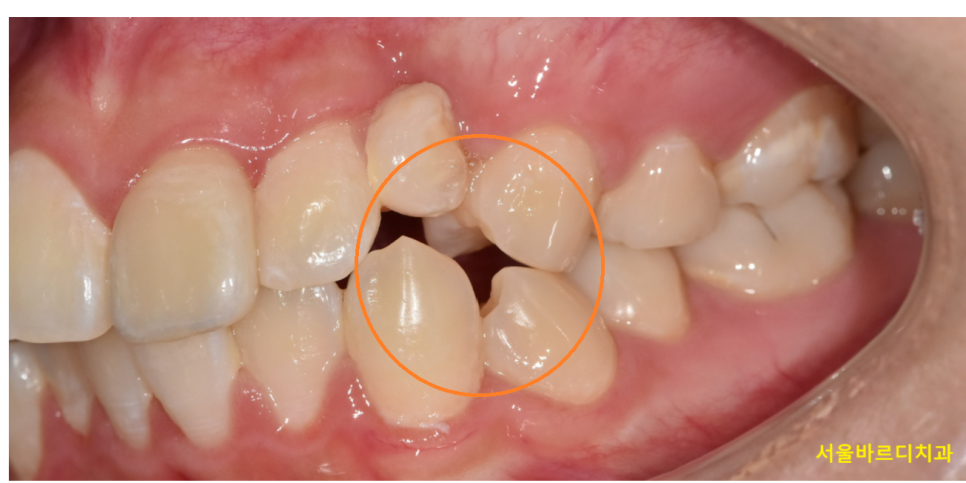

250328 정중선이 안맞는 경우

사람 얼굴이 비대칭일 수도 있고

치아가 결손됐을 수도 있고

여러 원인으로 중심선이 1-2mm 정도 어긋나서

치료가 마무리 될 수 있는데요.

중심선이 어긋나있다고 반드시 교정이 잘못됐다고 단정할 수는 없습니다.